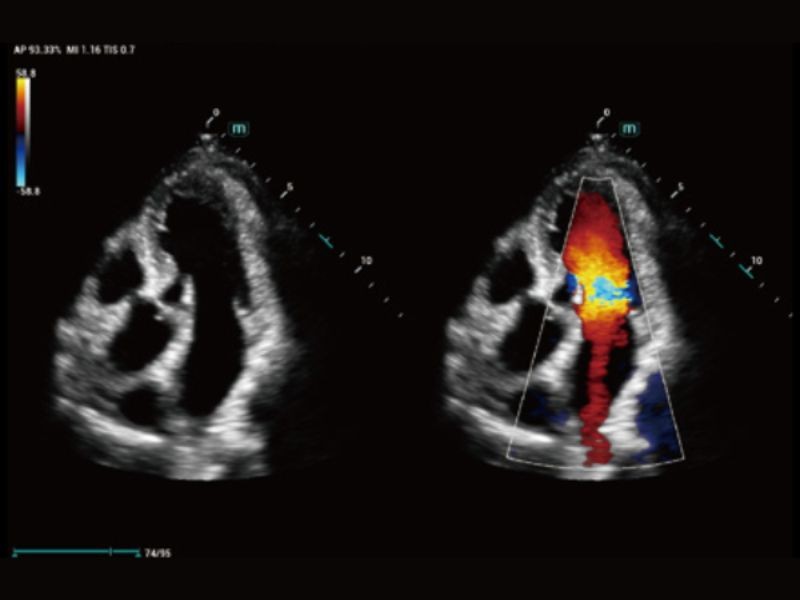

TTQA

Avaliação da sincronização miocárdica com análise quantitativa

AutoEF

Medição automática da fração de ejeção por quadros de diástole/sístole